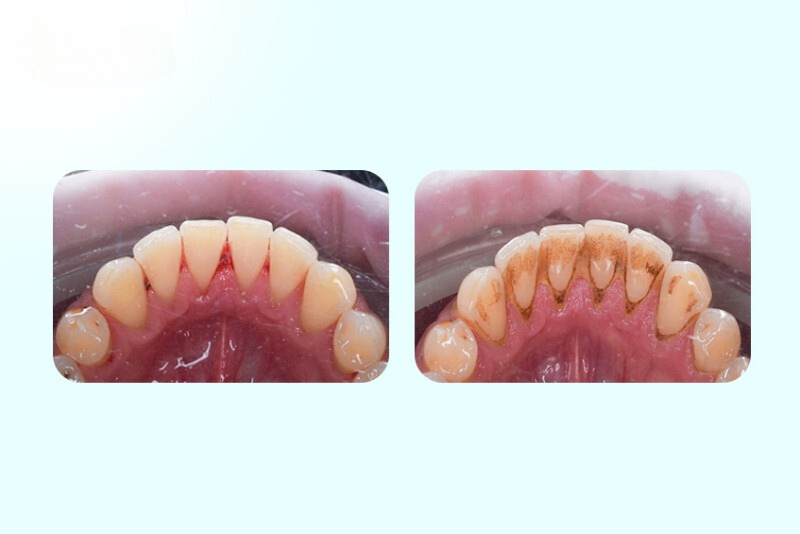

Cao răng không thể làm sạch hoàn toàn bằng cách chải răng và dùng chỉ nha khoa như bình thường. Cao răng hình thành phía trên viền nướu dễ dẫn đến sâu răng và hôi miệng.

Theo thời gian, cao răng gây ra các bệnh nướu răng tiến triển, nhẹ nhất là viêm nướu. Vôi răng có thể được ngăn chặn và khắc phục nếu bạn đánh răng, dùng chỉ nha khoa, sử dụng nước súc miệng sát trùng và được nha sĩ làm sạch thường xuyên.

Nếu không được loại bỏ và vệ sinh đúng cách, cao răng sẽ gây viêm nướu, hình thành các túi giữa nướu và răng do nhiễm vi khuẩn, và tiến triển thành bệnh nha chu. Khi bị bệnh nha chu, hệ thống miễn dịch sẽ phản ứng để chống lại vi khuẩn, khiến tình trạng viêm nướu trở nên tồi tệ hơn. Viêm nha chu có thể làm hỏng xương và các mô giữ răng, dẫn đến mất răng. Bệnh còn tác động tiêu cực đến sức khỏe tim mạch.

Có thể dễ dàng phát hiện sự tích tụ cao răng trên bề mặt răng, vì chúng thường có màu vàng hoặc nâu. Trong quá trình kiểm tra và làm sạch răng định kỳ, chuyên gia nha khoa sẽ phát hiện và loại bỏ cao răng.